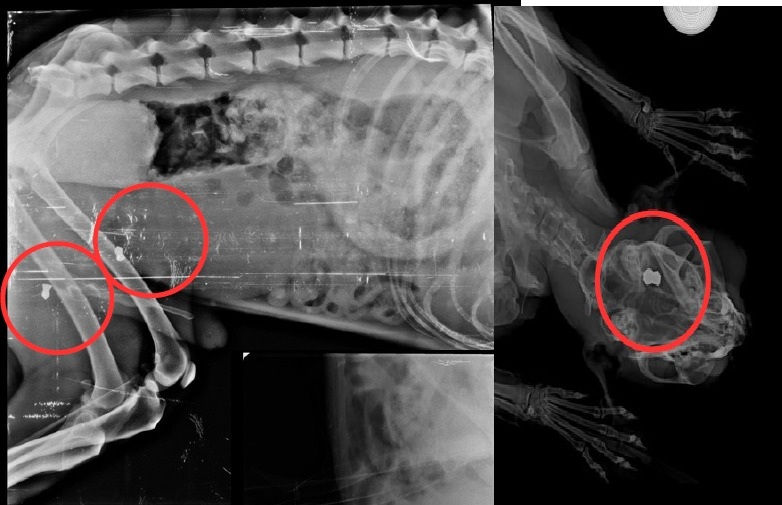

As investigações tiveram início após relatos de moradores da região, informando que cães e gatos vinham retornando para suas residências com ferimentos, aparentemente provocados por disparos de armas de pressão (chumbinhos). Durante as buscas, os policiais encontraram na residência do suspeito uma espingarda de pressão, uma pistola de pressão, diversas munições (chumbos), além de uma armadilha artesanal destinada à captura de animais de pequeno porte.